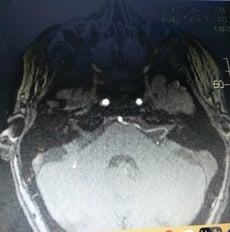

Blood vessel (AICA) pressing on the vestibular nerve